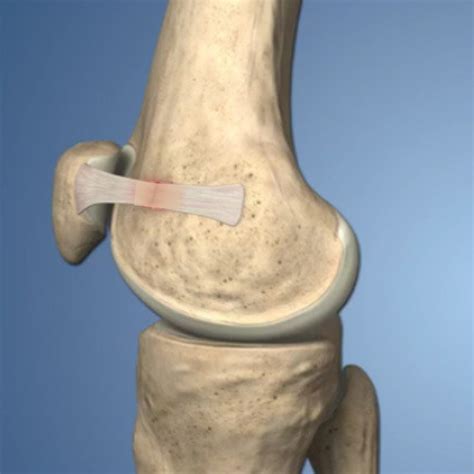

The MPFL is a thin, fibrous band that connects the medial (inner) side of the patella to the medial femoral condyle, which is the rounded part of the femur (thighbone) that articulates with the tibia (shinbone). The primary function of the MPFL is to stabilize the patella, keeping it aligned within the trochlear groove of the femur. This alignment is crucial for the smooth and efficient movement of the knee joint.

• Patellar Dislocation: This occurs when the patella slips out of the trochlear groove, often to the lateral (outer) side of the knee. The MPFL is typically torn or stretched during a patellar dislocation, leading to instability and recurrent dislocations.

• MPFL Tears: These can occur due to trauma, such as a direct blow to the knee or a sudden twisting motion. MPFL tears can range from partial to complete and may require surgical intervention depending on the severity.